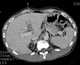

Traumatic liver cyst